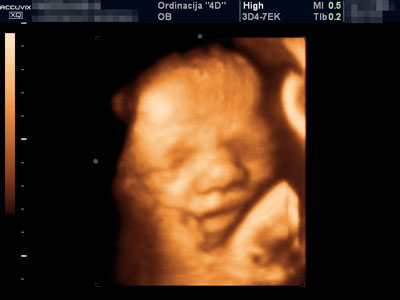

• www.4dordinacija.com ŠTA JE 4D ULTRAZVUK? Ultrazvuk koji nudi četvorodimenzionalan prikaz ploda. Šta to zapravo znači? Direktan uvid u dešavanja u majčinom stomaku tj. „live“ (uživo) prikaz izgleda i ponašanja ploda. Dakle, 4D je najsavremeniji prozor u bebin svet. ZAŠTO 4D? Zato što nudi mnogo više od samo „lepe slike“. Višestruko povećava mogućnost potvrđivanja normalnosti razvoja ploda u rizičnoj trudnoći, kao i rano otkrivanje neočekivanih abnormalnosti ploda. Lice, šake i stopala, česte su mete pojave izolovanih neočekivanih abnormalnosti (koje mogu i ne moraju biti genski uslovljene). Njihov fascinantan prikaz pri 4D pregledu ne dozvoljava propust, što ovaj pregled čini superiornim u odnosu na dosadašnje tradicionalne preglede. Dakle, 4D ultrazvuk obezbeđuje novu dimenziju infor...